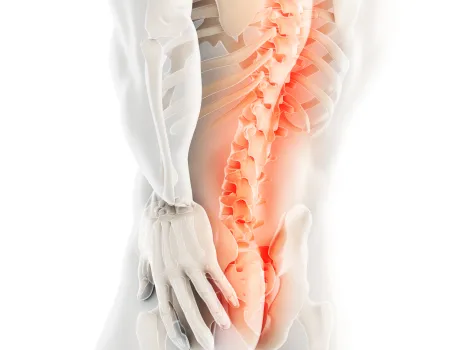

발의 문제는 전신통증의 시작입니다.

발은 우리 몸에서 건물의 주춧돌과 같은 역할을 합니다. 발의 틀어짐으로 인한 통증은 단순히 발의 문제로 그치지 않고 보행 패턴을 무너뜨리며 다리와 무릎 관절, 나아가 골반과 허리의 추간판까지 연쇄적인 영향을 미칩니다. 발의 문제를 조기에 발견해 치료하는 것이 전신 건강을 위해 중요합니다.

▲ 발의 문제로 인해 생기는 요통